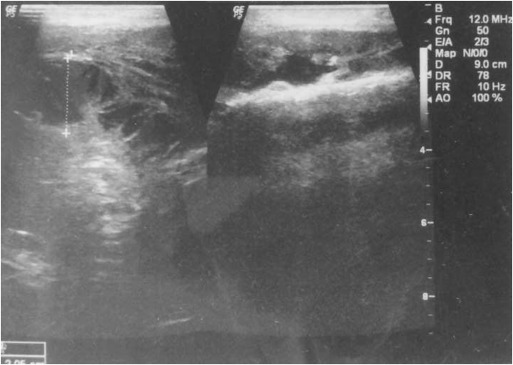

Fig. 8

Fig. 8.

Ultrasound images to see the relation of hematoma to the surrounding structures and evaluate the origin.

Fig. 9

Fig. 9.